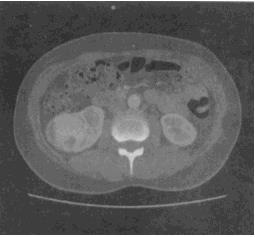

患者,52岁。无痛性血尿4天。双侧肾区CT平扫加增强扫描如图所示。最有可能的诊断是()。

A、肾囊肿

B、肾结核

C、肾错构瘤

D、肾盂癌

E、肾癌

E